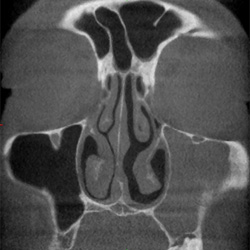

Volumenbestimmung

der Kieferhöhlen